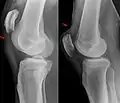

| An x-ray demonstrating quadriceps tendon rupture. Note the abnormal angle of the patella and soft-tissue swelling marked by the arrow. | |

X-ray of a tear of the patellar tendon. On the left: The kneecap is pulled up. On the right: Significant dent in the soft tissue above the kneecap.